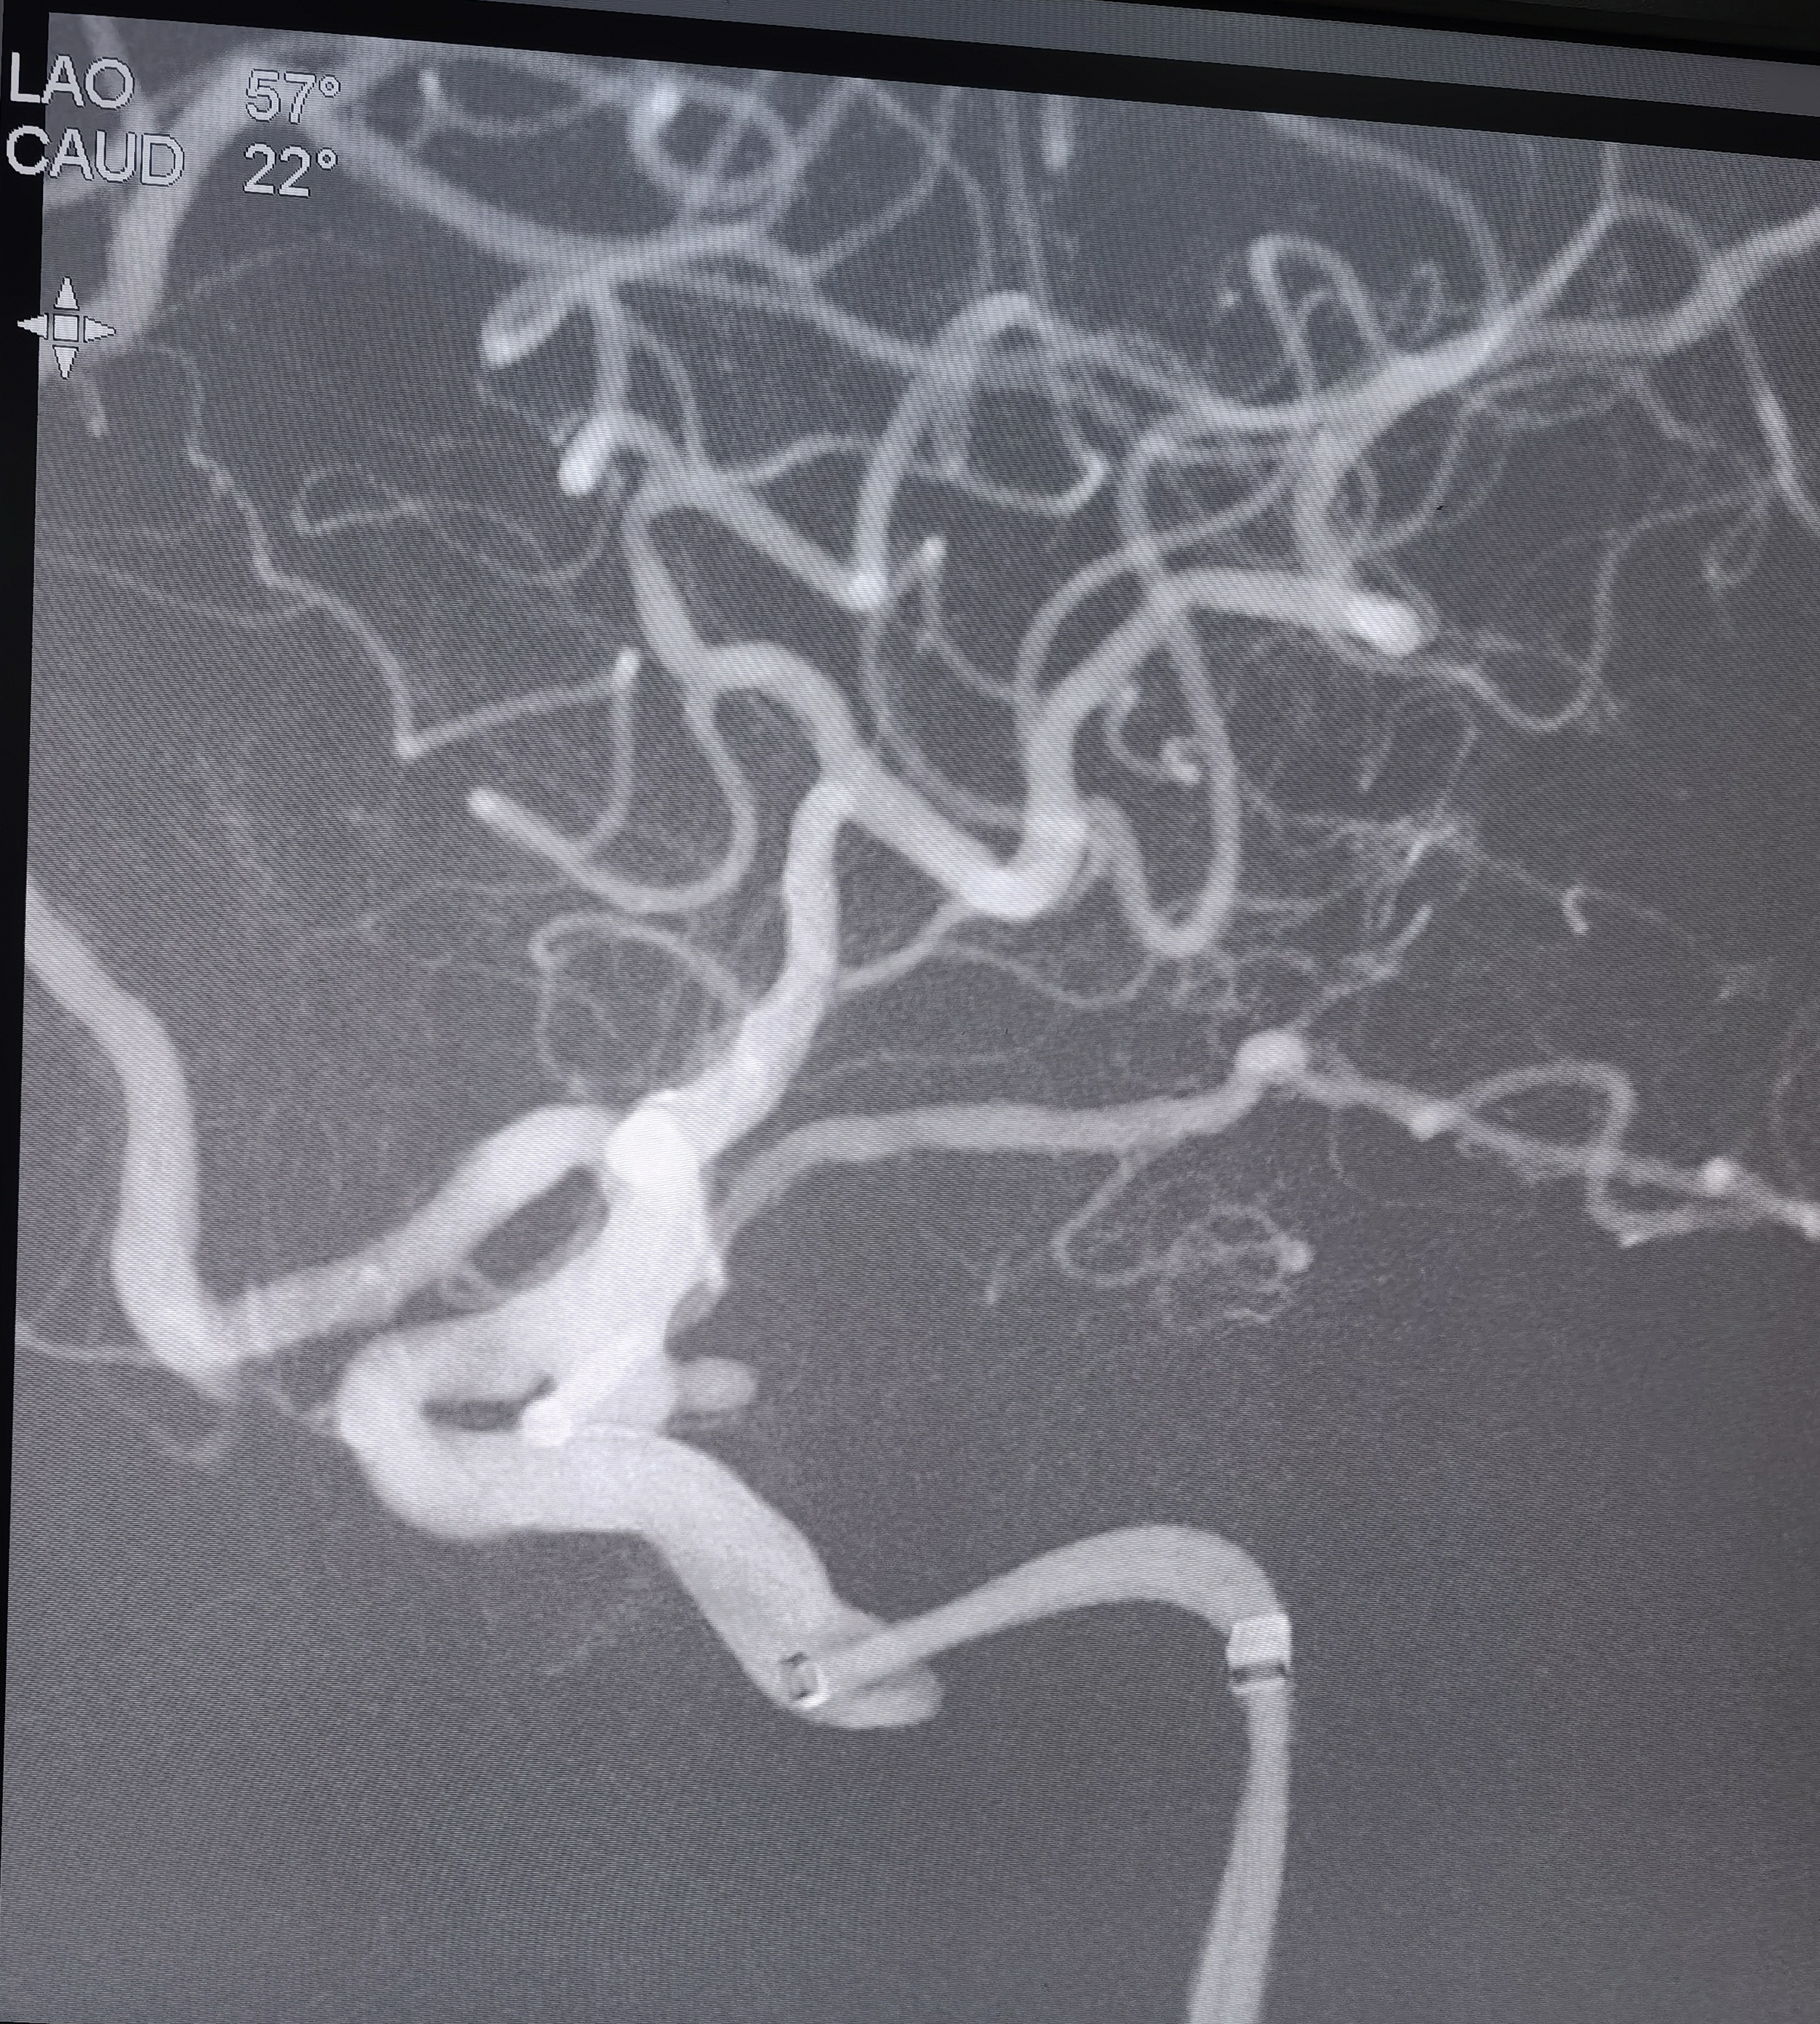

你的浏览器不支持video标签. 入院CT 血管迂曲你的浏览器不支持video标签. RCCA正位,胚胎型大脑后动脉,右侧大脑前动脉纤细。你的浏览器不支持video标签. RCCA3D造影你的浏览器不支持video标签. 右侧3D 右侧后交通动脉瘤形状亦不规则,拟二期治疗。你的浏览器不支持video标签. LCCA正位,胚胎型大脑后动脉,左侧A1供应双侧大脑前动脉。你的浏览器不支持video标签. LCCA3D造影你的浏览器不支持video标签. 左侧3D你的浏览器不支持video标签. 左椎正位,PICA以远未显影。 左侧后交通动脉瘤形状不规则,见子瘤。 拟支架辅助栓塞左侧后交通动脉瘤。 工作位路图,显示子瘤。 微导管首先超选子瘤填塞弹簧圈后,弹簧圈从子瘤脱出,遂应用支架于颈内动脉交通段释放辅助栓塞。你的浏览器不支持video标签. 术中造影你的浏览器不支持video标签. 术中造影你的浏览器不支持video标签. 术中造影你的浏览器不支持video标签. 释放支架,术中造影。你的浏览器不支持video标签. 术后造影你的浏览器不支持video标签. 术后正位你的浏览器不支持video标签. 术后侧位